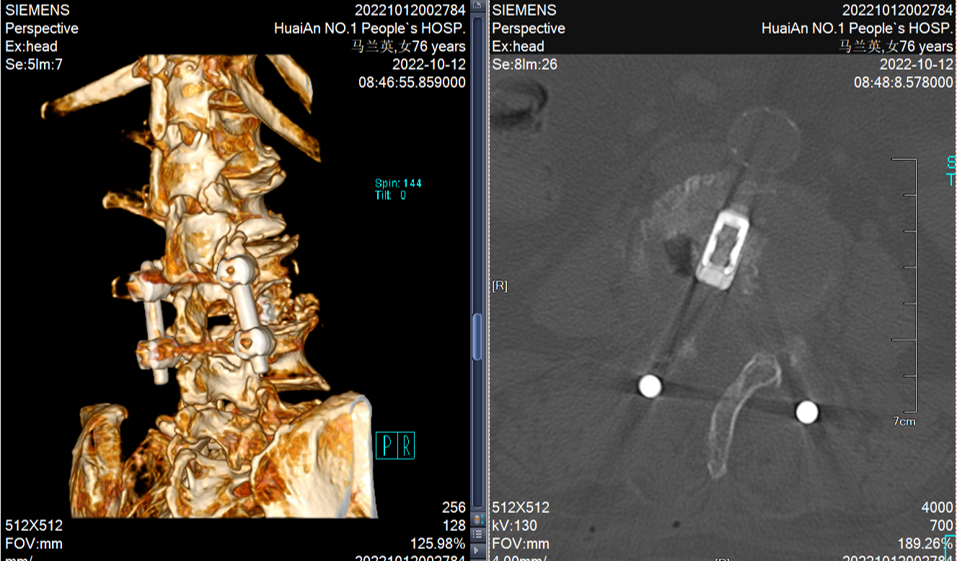

本团队率先开展腰椎微创内镜下减压融合术

有效解决了部分高龄患者不能耐受大手术(开放手术)的问题

在目前累计开展的130例内镜下腰椎减压融合手术中

有多名80岁以上患者受益

内镜下减压融合手术,既可以解决神经受压问题,又提供了长久的稳定性维持作用

手术出血控制在50ml以内,术后2-3天下床活动,避免老年患者长期卧床的并发症